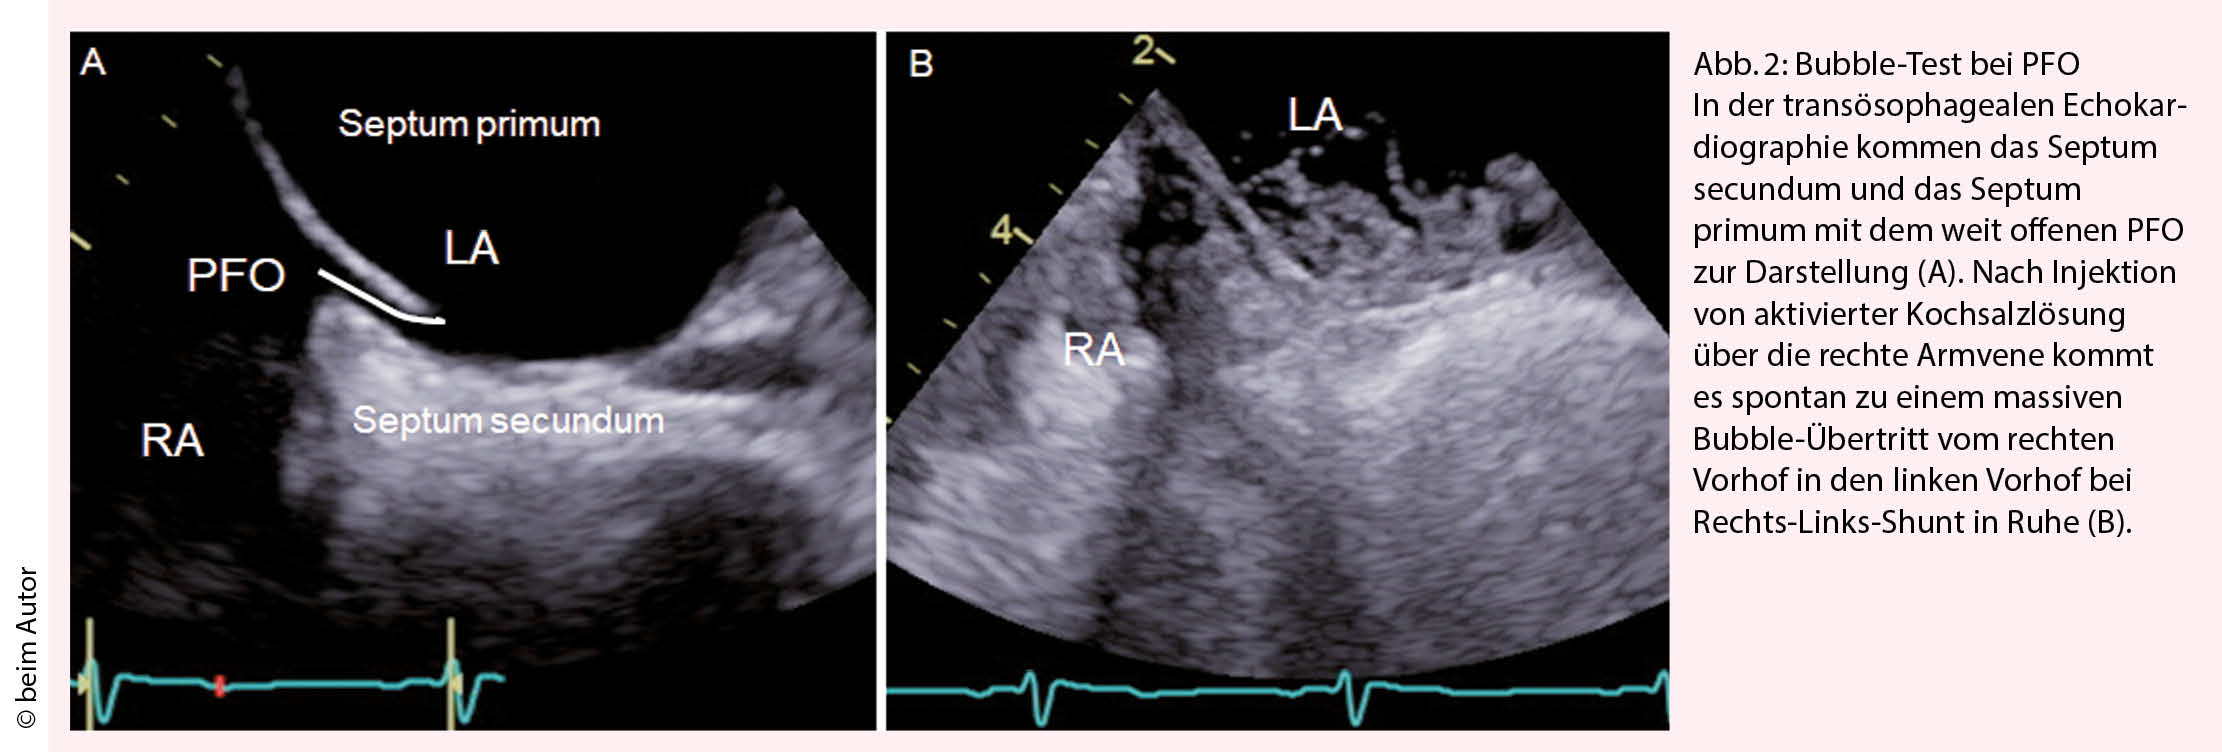

Das Elektrokardiogramm oder ein Langzeit-EKG von 24 bis 72 Stunden, ev. auch eine Langzeitaufzeichnung, sind nötig, um ein Vorhofflimmern auszuschliessen. Die Wahrscheinlichkeit, dass ein okkultes Vorhofflimmern vorliegt, ist altersabhängig. Bei jungen Patienten mit normaler Herzfunktion ist das Vorhofflimmern eine Rarität. Bei Patienten über 60 Jahren oder bei vergrösserten Vorhöfen wird die Wahrscheinlichkeit, dass ein Vorhofflimmern vorliegt, höher und die entsprechende Suche nach Vorhofflimmern wichtiger. Die transthorakale Echokardiographie dient zum Ausschluss einer kardio-embolischen Quelle. Liegt keine Pathologie am Myokard oder den Klappen vor oder besteht der Verdacht auf eine paradoxe Embolie durch das PFO wird eine transoesophageale EchokardioÂgrafie (TEE) angeschlossen. Meist wird bereits bei der transthorakalen Echokardiografie, sicher aber bei der TEE ein Bubble-Test durchgeführt (Abb. 2) um festzustellen, ob ein Rechts-Links-Shunt in Ruhe vorliegt oder mittels eines Valsalva Manövers provoziert werden kann. Die TEE ermöglicht zum einen den Ort des Rechts-Links-Shunts zu eruieren, zum anderen Shuntvitien wie ein Vorhofseptumdefekt, falsch mündende Lungenvenen oder eine pulmonale A-V Malformation auszuschliessen. Mittels TEE wird die Morphologie und Anatomie des PFO und des Vorhofs visualisiert, was wichtig ist für einen eventuellen PFO Verschluss. Die Evaluation der Grösse des PFOs in der TEE ist jedoch problematisch, da das Septum primum deckelförmig mehr oder weniger aufgeht und der Bubble-Übertritt damit von der Qualität des Valsalva-Manövers abhängt (Abb. 2). In der TEE kommt in der 2-D Darstellung die schlitzförmige Öffnung des PFO meist als kleine Lücke von 1-4 mm zur Darstellung. In Wirklichkeit variiert die anatomische Grösse des PFO von 4 bis 16 mm, im Mittel beträgt sie 8 ± 3 mm (6, 7).